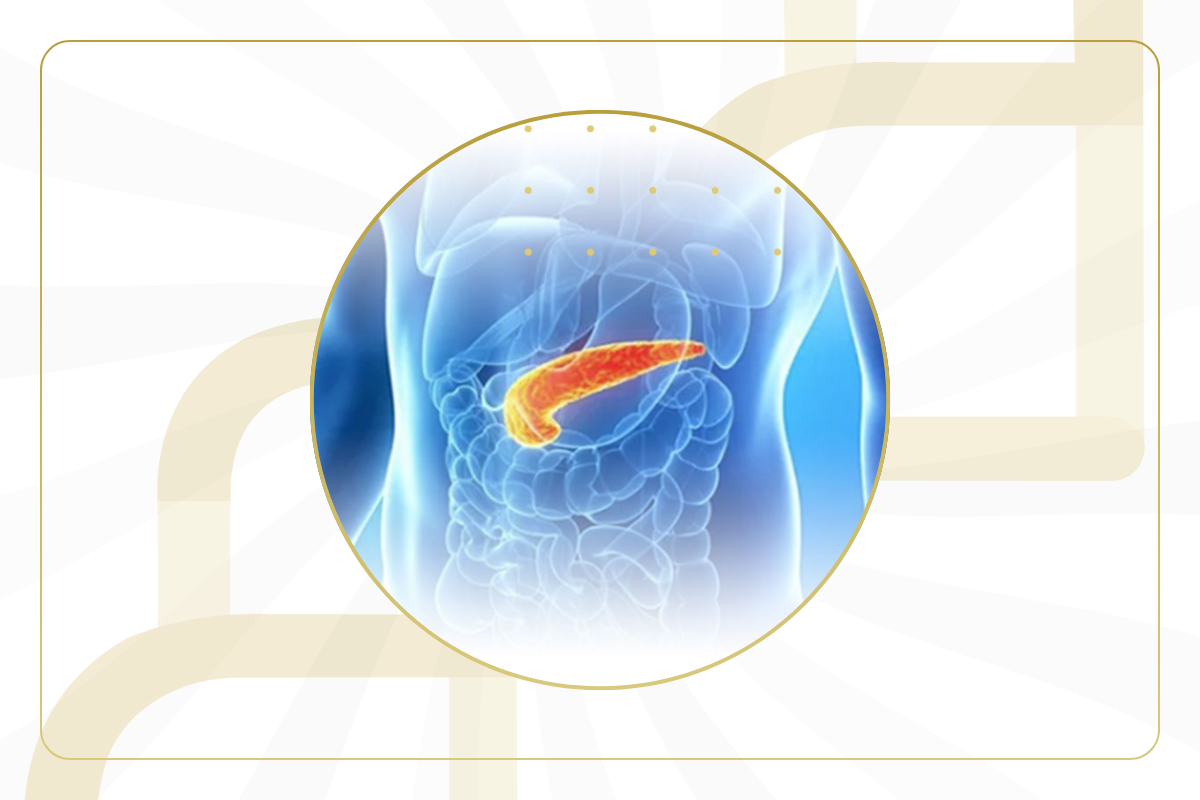

التهاب البنكرياس قد يظهر بصورة&nbs...